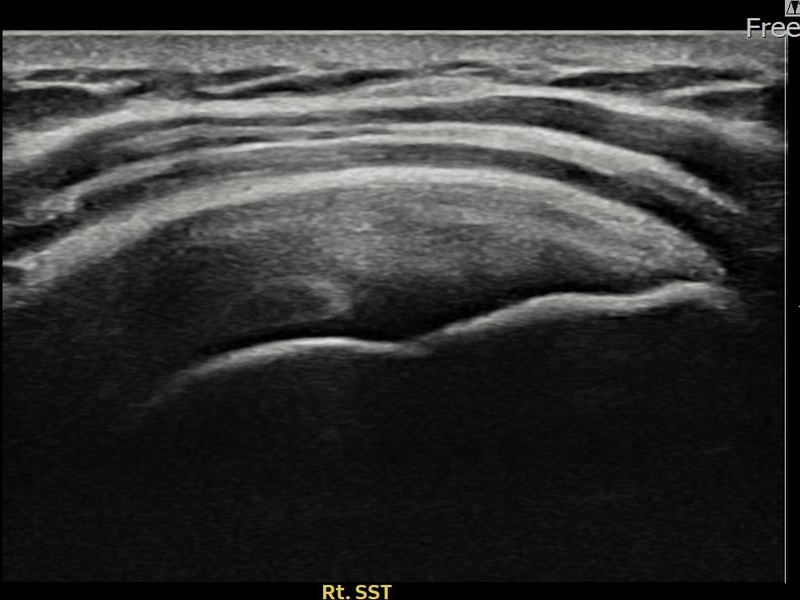

유ㅇㅇ님 · 우측 견갑하근건 관절면측 부분파열

우측 어깨 전방 통증과 팔 내회전 제한으로 내원하셨습니다. 초음파 검사에서 견갑하근건 관절면측 부분파열이 확인되었으며, 어깨인대 축소봉합술 후 힘줄 구조적 안정화가 이루어졌습니다.

유ㅇㅇ님 · 우측 견갑하근건 부분파열

우측 어깨 전방 통증과 팔 들어 올리기 어려움으로 내원하셨습니다. 초음파 검사에서 견갑하근건 부분파열이 확인되었으며, 어깨인대 축소봉합술 후 힘줄 연속성이 회복되고 어깨 기능이 정상화되었습니다.